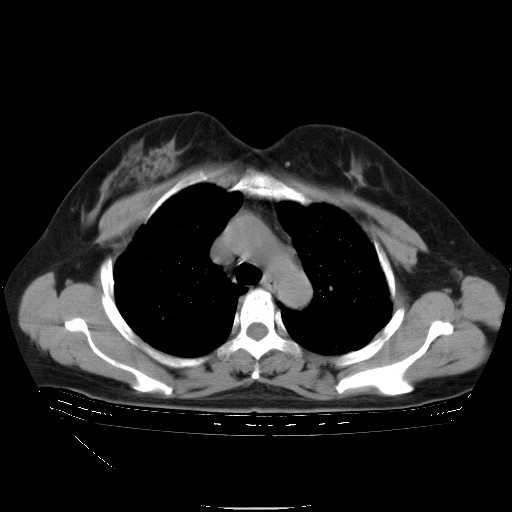

下面是今天刚刚做的,在上海治疗,吃了家属也说不清的一种药,一个月1万左右,

考虑  腺癌肺内转移,治疗较前病灶缩小、减少

肺癌并肺内转移,这种疾病治疗后在影像上看略有好转,不是很显著,但是肿瘤治疗效果影像只是一方面。

效果还可以.

标准的细支气管肺泡癌呀!治疗后病情有所控制,也没治愈的迹象!

有点效果.

应该是比较典型的细支气管炎,4个月的时间不说明问题;有时候疾病是有个相对稳定期的,如果喝10元一斤的茶叶估计也会这样。